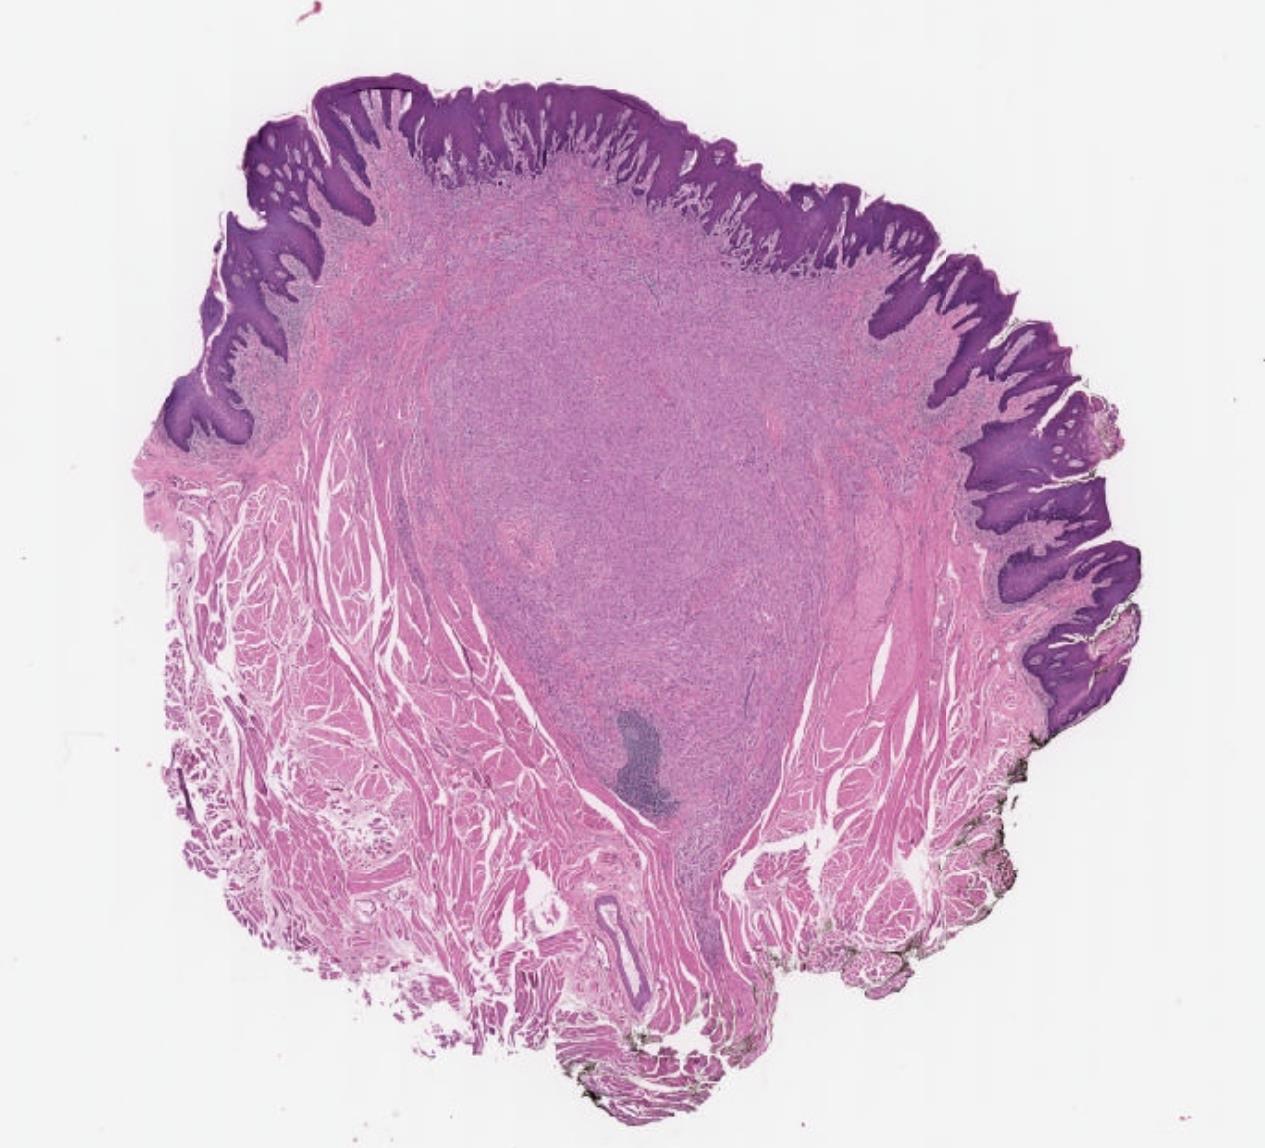

26-year-old, Female, Parotid tumour

Case 1- Salient points • Circumscribed salivary tumour, infiltrative periphery • Papillary cystic, microcystic patterns, hobnailing • Solid sheets of large polygonal cells with granular eosinophilic cytoplasm and vesicular nuclei • Secretory material –colloid-like eosinophilic secretions • Occasional mitotic figures • Work up? PAS, DPAS, • CK7, S100, DOG1, Mammoglobin

Case 1 Diagnosis

Secretory carcinoma

Discussion Differential diagnoses • Acinic cell carcinoma • Secretory carcinoma (previously called MASC) • MEC • 90% -ETV6::NTRK3 fusion -chromosomal rearrangement, t(12;15) (p13;q25) • ETV6::RET, ETV6::MET, ETV6::MAML3 • ETV6 translocation-negative secretory carcinoma. • Similar to Acinic cell carcinoma • But S100+, Mammoglobin+, DOG1-

5th ed Essential and desirable diagnostic criteria • Essential: single cell type with vacuolated colloid-like secretory material; no zymogen cytoplasmic granules; IHC positivity for S100 protein, SOX10, and mammaglobin; lack of IHC staining for p40 and/or p63 • Desirable: ETV6 or RET rearrangement demonstrated by FISH, RNA sequencing, or PCR • Low grade • Lymph node metastases are reported in as many as 25% of cases